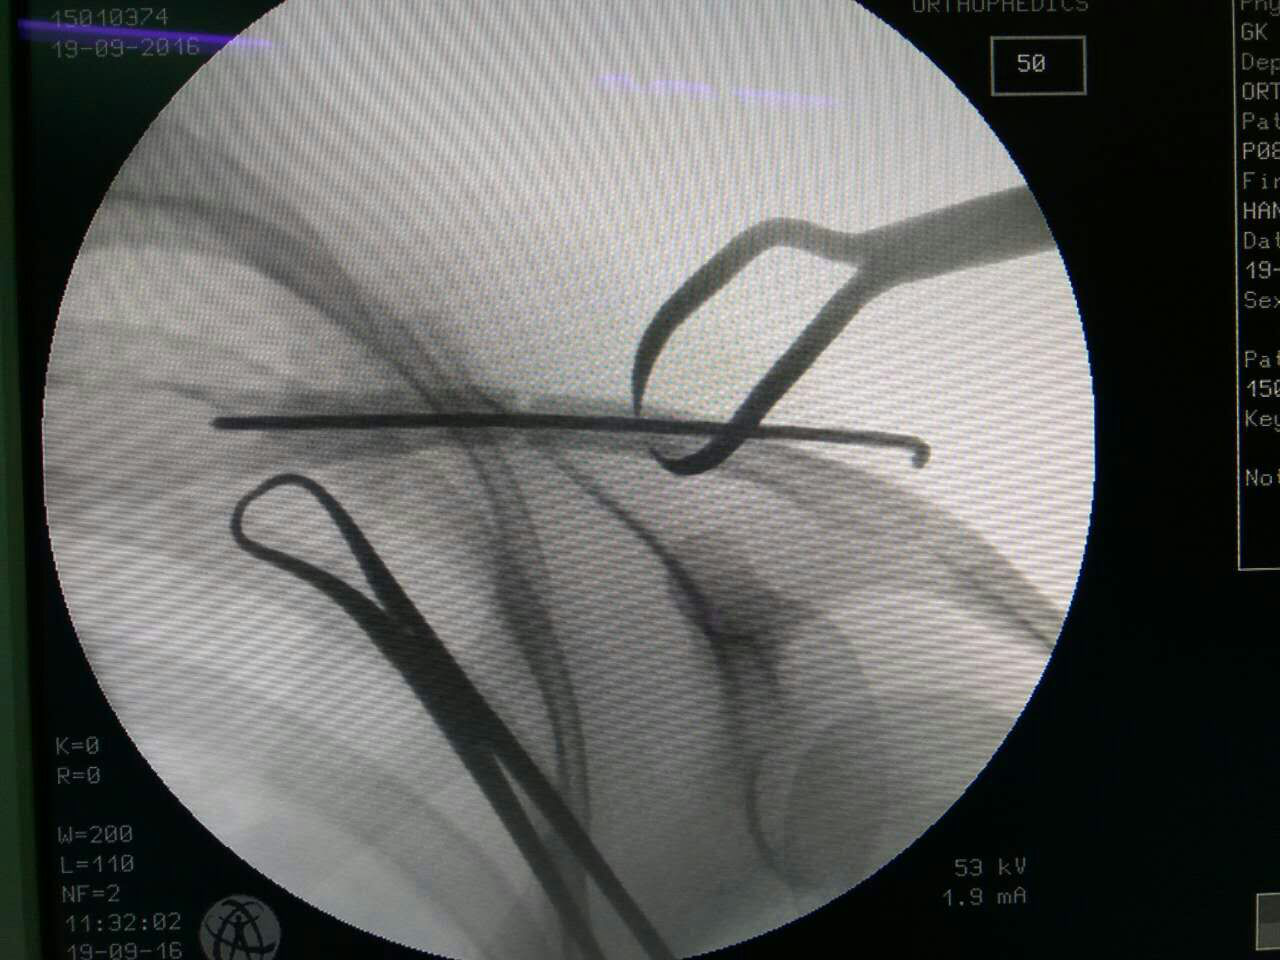

手术由王健民副主任医师、张成勇主治医师、张岭住院医师合作进行。在C型臂X线机的透视下,使用专用锁骨端提钳夹持牵引,中医传统手法复位骨折断端,用2.0mm克氏针穿针固定锁骨。术后,患者的颈肩部仅留下几个细小针眼,愈合后不留疤痕。术后患者十分满意,恢复良好。